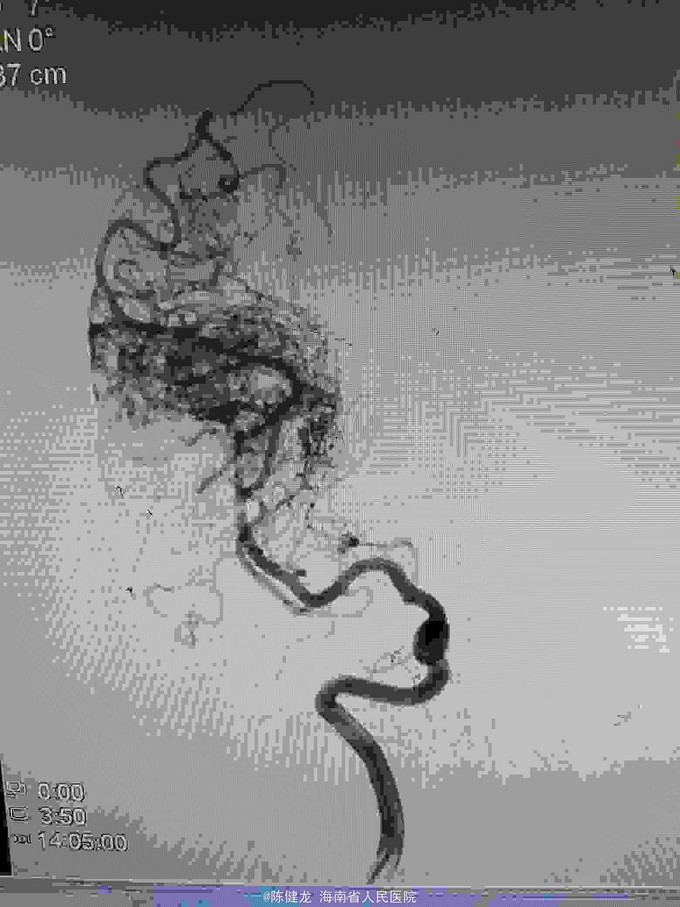

AVM

右颞大型AVM,大脑中主要供血。

右颞AVM

己进行二次治疗,拟近期内进行第三次治疗。争取80%至90%栓塞,残留部分伽玛刀治疗。